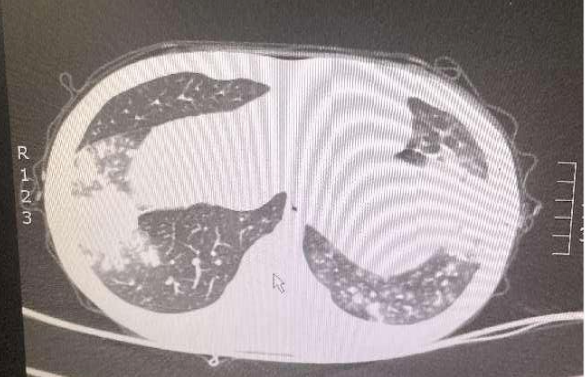

7岁男童,因“发热、咳嗽5天”入院。院前以高热为主,已予治疗,患儿体温无好转,查肺部CT示双肺炎症。急需完善支气管镜肺泡灌洗术,并送检病原学明确病因。